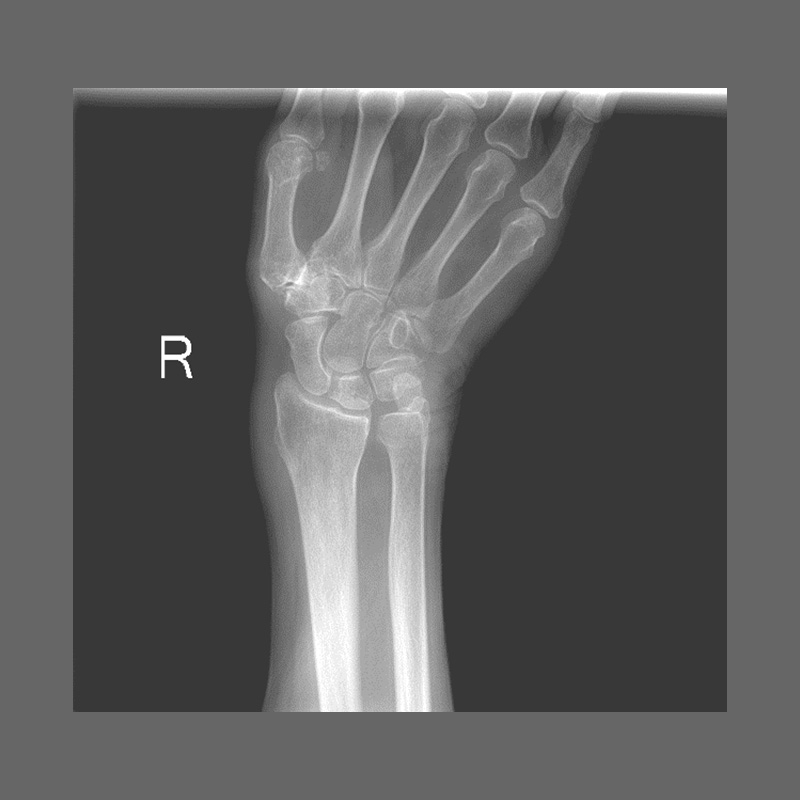

КЛІНІЧНА ГАЛЕРЕЯ GENÈVE 40M: